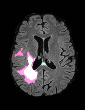

In recent years, data-driven machine learning (ML) methods have revolutionized the computer vision community by providing novel efficient solutions to many unsolved (medical) image analysis problems. However, due to the increasing privacy concerns and data fragmentation on many different sites, existing medical data are not fully utilized, thus limiting the potential of ML. Federated learning (FL) enables multiple parties to collaboratively train a ML model without exchanging local data. However, data heterogeneity (non-IID) among the distributed clients is yet a challenge. To this end, we propose a novel federated method, denoted Federated Disentanglement (FedDis), to disentangle the parameter space into shape and appearance, and only share the shape parameter with the clients. FedDis is based on the assumption that the anatomical structure in brain MRI images is similar across multiple institutions, and sharing the shape knowledge would be beneficial in anomaly detection. In this paper, we leverage healthy brain scans of 623 subjects from multiple sites with real data (OASIS, ADNI) in a privacy-preserving fashion to learn a model of normal anatomy, that allows to segment abnormal structures. We demonstrate a superior performance of FedDis on real pathological databases containing 109 subjects; two publicly available MS Lesions (MSLUB, MSISBI), and an in-house database with MS and Glioblastoma (MSI and GBI). FedDis achieved an average dice performance of 0.38, outperforming the state-of-the-art (SOTA) auto-encoder by 42% and the SOTA federated method by 11%. Further, we illustrate that FedDis learns a shape embedding that is orthogonal to the appearance and consistent under different intensity augmentations.